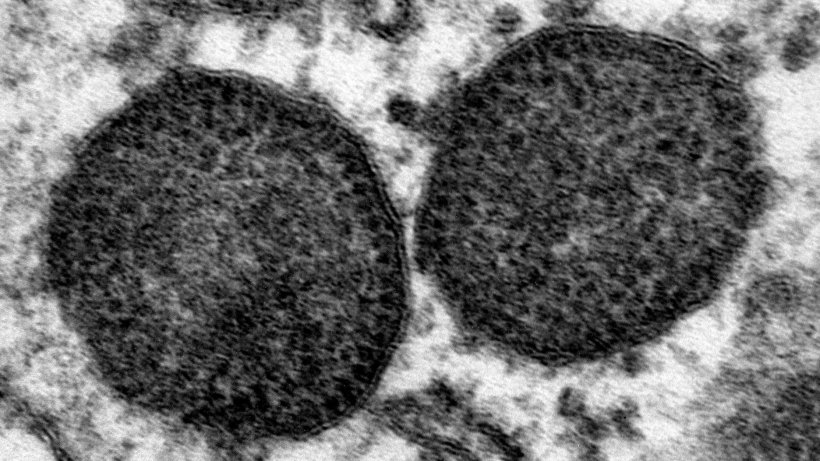

J Gen Virol. 2015 Jul;96(Pt 7):1830-41. doi: 10.1099/vir.0.000100. Epub 2015 Feb 23. Global molecular genetic analysis of porcine circovirus type 2 (PCV2) sequences confirms the presence of four main PCV2 genotypes and reveals a rapid increase of PCV2d. Xiao CT, Halbur PG, Opriessnig T.

Foram analisados e comparados 1680 ORF2 (open reading frame 2) de PCV2 utilizando diferentes métodos estatísticos para avaliar a relação filogenética das estirpes de PCV2.

O estudo confirmou que PCV2 pode dividir-se em 4 sub-tipos principais: PCV2a, PCV2b, PCV2c e PCV2d. Além disso, os autores descreveram 6 clados intermédios mais pequenos entre estes sub-tipos. Um destes clados intermédios parece estar limitado à Ásia. No entanto, foram descritas estirpes deste clado de um modo constante, pelo que pode ser considerado um clado activo. Os outros clados intermédios incluem um número muito limitado de estirpes pelo que podem ser considerados inactivos. Podem ser representados pequenos grupos extintos de estirpes que mostraram pouca vitalidade, estirpes intermédias da evolução do vírus ou artefactos das análises. O PCV2c parece ser um grupo extinto de vírus. A afiliação de estirpes individuais a diferentes genótipos e clados intermédios depende por vezes do modelo estatístico utilizado e do número de estirpes de referência utilizadas na análise.

Os resultados também confirmam que houve duas grandes alterações de um subtipo para outro: em 2003, antes do uso das vacinas contra PCV2, houve mudança de PCV2a a PCV2b e a segunda mudança foi de PCV2b a PCV2d, que nos EUA se produziu principalmente entre 2011 e 2014.

As análises filogenéticas adicionais sugerem que tanto PCV2b como PCV2d evoluiram independentemente entre si desde há mais de 20 anos. Dentro de cada subtipo há uma divergência genética gradual. O motivo pelo qual PCV2 tem uma elevada taxa de mutação e tanta diversidade genética, pouco frequente nos vírus DNA, é desconhecido. Também não se conhecem as causas do constante aparecimento de estirpes nem das alterações de genótipos observadas. A primeira mudança ocorreu antes da introdução das vacinas contra PCV2.

Este estudio demonstra que o PCV2 evolui muito mais rápido e é muito diverso em comparação com outros vírus DNA. A indústria suína deve manter-se alerta, monitorizar a evolução do PCV e determinar a sua relevância para o controlo de PCVD.